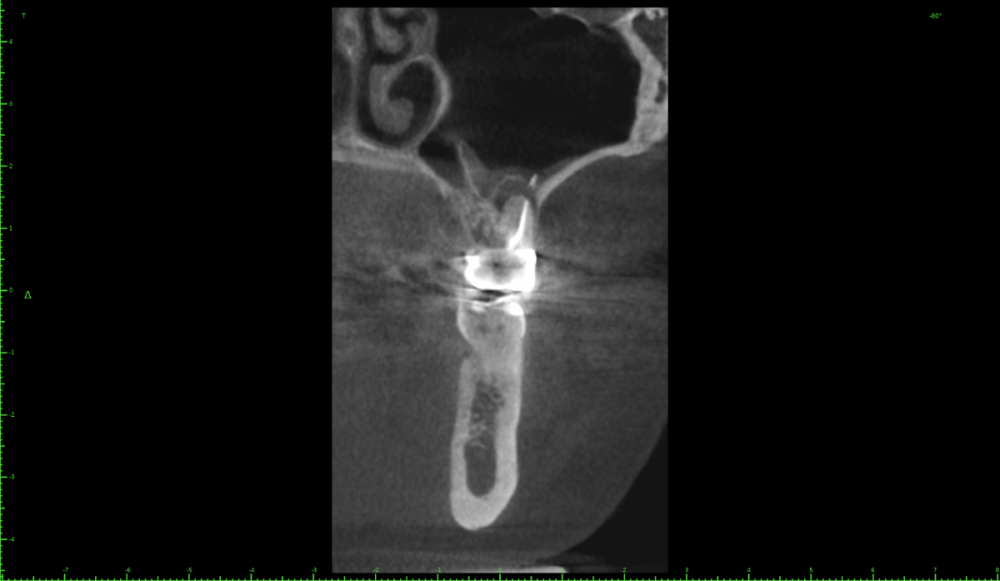

Katya88 Опубликовано 28 июля, 2021 Поделиться Опубликовано 28 июля, 2021 Мой стоматолог терапевт советует удалить, так как там кисты, а ортопед советует найти того, кто займется лечением. КТ прилагаю https://drive.google.com/file/d/1Z-neEH63BszTXxa8bAOG1tgsrIrsqrVK/view?usp=drive_web Ссылка на комментарий

Женька Опубликовано 28 июля, 2021 Поделиться Опубликовано 28 июля, 2021 2.6 2.7 3.7 На 3.5 и 1.5 стоит обратить внимание 1.5 1 Ссылка на комментарий

Женька Опубликовано 28 июля, 2021 Поделиться Опубликовано 28 июля, 2021 54 минуты назад, Katya88 сказал: 1.5 менять коронку как минимум снять существующую конструкцию и посмотреть клинически на зуб(ы). 1.5 на КТ выглядит удручающе. По остальным, я бы поддержал ортопеда и попытался зубы сохранить. Пусть коллеги меня поправят. 1 1 Ссылка на комментарий